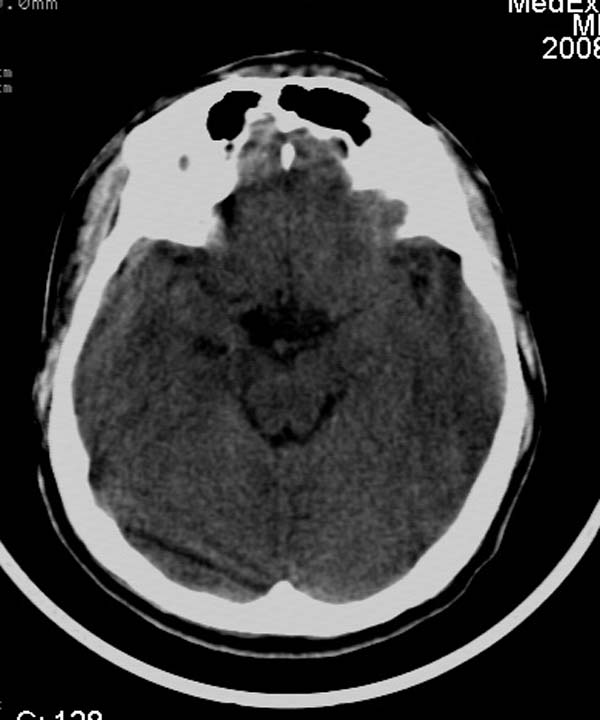

患者,男,24岁。头面部外伤后意识障碍1小时。

小脑幕缘密度增高,考虑有少量出血,建议复查

考虑右侧天幕缘少量蛛网膜下腔出血;建议:必要时复查。

1)考虑少量蛛网膜下腔出血;建议:必要时复查。2)桥前池及左侧环池表皮样囊肿可能。建议:行mri检查。

1)考虑蛛网膜下腔出血;建议:复查。2)桥前池及左侧环池表皮样囊肿可能。建议:行mri检查。

考虑右侧天幕缘区域少量蛛网膜下腔出血。

一侧密度增高,是否考虑为硬膜下血肿,前额血肿真好对冲伤,桥小脑脚增宽建议进一步检查